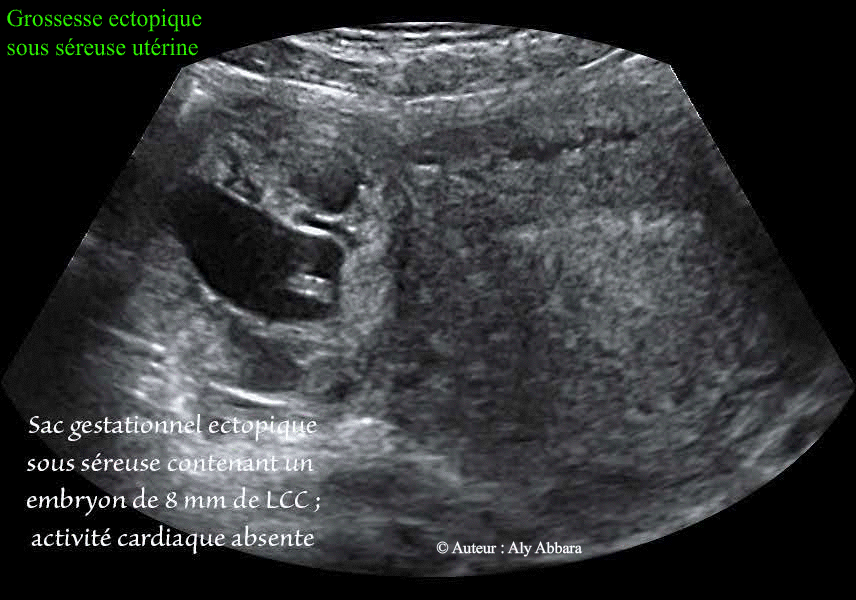

• Images échographiques par voie endovaginale montrant un sac gestationnel d'une grossesse débutante implantée à l'extérieur de la corne utérine droite du corps utérin, et à l'extérieur du myomètre (absence de couche myométriale autour du sac gestationnel permettant d’exclure le diagnostic de grossesse ectopique interstitielle ou cornuale).

• Ce sac gestationnel mesure 41,5 x 37,1 x 41,9 mm de diamètres (soit 33,8 cm3) ; il contient une vésicule ombilicale et un embryon de 8 mm sans activité cardiaque (donc grossesse arrêtée à 6+5 SA) ; le dosage de β-hCG plasmatique était égal à 65 500 UI/l.

• La cœlioscopie permet de constater qu'il s'agit d'une localisation inhabituelle de la grossesse extra-utérine : sac gestationnel évoluant sous la séreuse utérine, sur la paroi postérieure du corps utérin, en arrière de la jonction utéro-tubaire droite. De ce fait, la trompe droite paraissait tout à fait normale sur la totalité de sa longueur ; elle n'est pas concernée par cette grossesse ectopique juxtaposée.

La description anatomique retenue puis confirmée après exérèse chirurgicale est celle « d'une grossesse ectopique sous séreuse utérine »